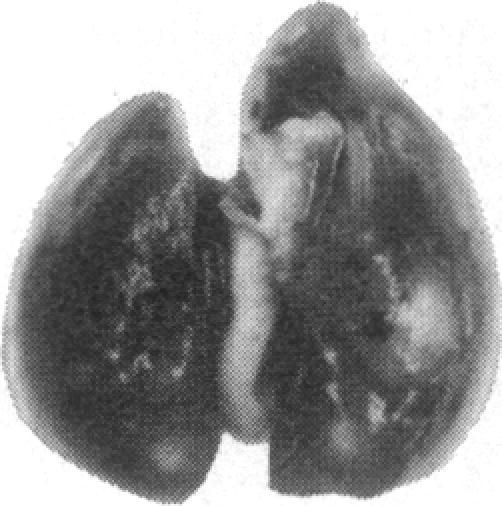

通过苦马豆素处理进行寡糖修饰可抑制B16-F10小鼠黑色素瘤细胞在肺部的定植。

Oligosaccharide modification by swainsonine treatment inhibits pulmonary colonization by B16-F10 murine melanoma cells.

Oligosaccharide moieties of cell-surface glycoconjugates are thought to be involved in recognition events associated with tumor metastasis and invasion. Using swainsonine (SW), an inhibitor of Golgi alpha-mannosidase II that results in the formation of hybrid-type oligosaccharides on N-linked glycoproteins, we have tested the hypothesis that specific glycan structures are required for pulmonary colonization by tumor cells. B16-F10 murine melanoma cells were treated with SW in growth medium and then injected intravenously into syngeneic C57BL/6 mice. This treatment resulted in dramatic inhibition of colonization, but it had no effect on B16-F10 viability or on cellular tumorigenicity after subcutaneous implantation. SW-treated radiolabeled B16-F10 cells were cleared from the lungs at a greater rate than control cells, suggesting that one effect of treatment is to alter tumor cell retention in the target organ. Our results implicate specific glycan structures in pulmonary colonization and offer a potential approach for identification of specific macromolecules involved in tumor cell-organ recognition during metastasis.

摘要

细胞表面糖缀合物的寡糖部分被认为参与了与肿瘤转移和侵袭相关的识别过程。我们使用了苦马豆素(SW),一种高尔基体α-甘露糖苷酶II的抑制剂,它会导致N-连接糖蛋白上形成杂合型寡糖,来检验肿瘤细胞在肺部定植需要特定聚糖结构这一假说。将生长培养基中的B16-F10小鼠黑色素瘤细胞用SW处理,然后静脉注射到同基因的C57BL/6小鼠体内。这种处理导致定植受到显著抑制,但对B16-F10细胞的活力或皮下植入后的细胞致瘤性没有影响。与对照细胞相比,经SW处理的放射性标记B16-F10细胞从肺部清除的速率更快,这表明处理的一个作用是改变肿瘤细胞在靶器官中的滞留情况。我们的结果表明特定聚糖结构与肺部定植有关,并为识别转移过程中参与肿瘤细胞-器官识别的特定大分子提供了一种潜在方法。